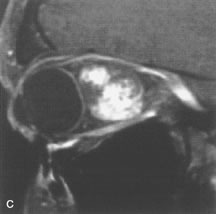

PATIENT PREPARATION Before MRI is performed, patients must be screened and prepared to avoid the potential hazards associated with the strong magnetic field. Patients who have ferrous aneurysm clips or cardiac pacemakers, who depend on life-support equipment, or who retain a possible metallic intraocular foreign body are not candidates for this imaging modality. MRI cannot be performed on obese patients who cannot fit into the bore of the magnet. Patients who are claustrophobic may not tolerate a prolonged period of study within the confines of the magnet, whereas others might do well if given a mild sedative. All worn metallic objects (e.g., necklaces, watches) should be taken off, credit cards set aside, and eye makeup removed before entering the room containing the magnet.5,20,34,35,36 NORMAL ORBITAL ANATOMY T1-weighted images provide the best anatomic details of the orbit because they display superior contrast resolution between normal structures (see Fig. 8). The vitreous has a long T1, resulting in an intermediate signal similar to brain, whereas the crystalline lens and sclera appear dark because of a longer T1 and short T2. The extraocular muscles, like all skeletal muscles, demonstrate a moderately long T1 and short T2 and highly contrast with the intense signal of the surrounding orbital fat (adipose tissue has an extremely short T1). The lacrimal glands appear as mottled areas of reduced intensity of the signal from the orbital fat in the lacrimal fossa. The optic nerves are seen with the same signal intensity as brain white matter and are hypointense relative to the orbital fat because their Tl is longer than the Tl of fat but shorter than the Tl of water. Cortical bone is not well delineated because it contains little free water, yielding minimal signal in MRI, and thus appears dark on all pulse sequences. This feature explains why MR images of the orbital apex and intracanalicular portion of the optic nerves are superior to comparable CT scans. Partial volume averaging of the bones in these regions obscures soft tissue details on CT images, whereas MRI reveals the signals only from the soft tissue structures with no cortical bone input. Bone marrow, on the other hand, is seen as a relatively intense signal because of its high fat content (see Fig. 8).37,38 T2-weighted pulse sequences are not ideal for imaging normal anatomy; however, they are particularly useful in revealing pathologic conditions (see Fig. 9). T2-weighted studies are most easily recognized by a bright vitreous signal. ORBITAL DISEASES Vascular Lesions Cavernous hemangiomas appear as well-circumscribed, smooth, usually intraconal masses that are isointense to muscle on T1-weighted images and hyperintense on T2-weighted images (Fig. 12). Patchy early enhancement is typically followed by diffuse, more homogeneous enhancement.39 The internal architecture of the mass, including septation and internal vasculature, may often be appreciated with high-quality orbital imaging.40 Lymphangiomas consist of ectatic vascular channels within a connective tissue stoma with varying degrees of lymphoid cellularity. On MRI, these tumors are typically poorly circumscribed, multicompartmental, and heterogeneous, often showing cystic dilations with fluid levels (Fig. 13). The signal characteristics within lymphangiomas vary considerably, reflecting cystic and solid components and the varying paramagnetic characteristics of blood at different stages of degradation.40–42 Acute hemorrhage appears hypointense on both T1- and T2-weighted formats. Methemoglobin present in subacute hemorrhage (3 to 14 days) leads to hyperintense signal on both T1- and T2-weighted images.41 A small percentage of lymphangiomas appear radiologically indistinct from orbital cavernous hemangiomas.43 Orbital varices are venous malformations that expand with increased systemic venous pressure, such as with Valsalva maneuvers. Because rapid acquisition of images during a Valsalva maneuver is important in imaging such a lesion, conventional or spiral CT is currently the modality of choice.44 MRI is an excellent modality for demonstrating enlargement of the cavernous sinus and dilation of the superior ophthalmic vein in patients with high-flow carotid-cavernous fistulas (Fig. 14).37MRA may be helpful in the evaluation of the venous outflow pattern. The rapidly flowing blood in these vascular structures carries the excited protons out of the section before they can be imaged, resulting in their dark appearance.5 In low-flow dural arteriovenous malformations, MRA may help define the arterial feeding vessels.45 Neural Lesions MRI is more effective than CT in delineating the intracranial optic nerves, chiasm, and optic tracts and, for this reason, is the preferred imaging modality in the evaluation of optic nerve disorders. The spatial relationships and image contrast of the orbital tissues with intraorbital optic nerve tumors is comparable between the two imaging modalities. The normal nerve is isointense to brain and appears enlarged and kinked owing to infiltration of an optic nerve glioma on T1-weighted images. Gliomas appear hyperintense on T2-weighted images and may be heterogeneous owing to cystic areas within the tumor. Contrast enhancement is variable.46 Intraorbital and intracranial optic nerve sheath meningiomas are usually isointense to cortical gray matter on Tl-weighted images and remain isointense on proton density studies (Fig. 15). Gd-DTPA is useful in delineating the intracranial extension of optic nerve meningiomas.7,47 The hyperostosis of bone and calcification associated with meningiomas are not demonstrated as well on MRI studies as on CT scans.20,37 Gd-DTPA–enhanced MRI also appears promising in the study of the permeability of the blood–brain barrier in selected optic neuropathies.22,48 MRI may reveal an enlarged optic nerve and some degree of contrast enhancement in cases of optic neuritis.49 Muscle Disorders Extraocular muscle enlargement in patients with thyroid-associated orbitopathy is demonstrated equally well with CT and MRI studies. However, the superior tissue contrast on MR images reveals better details of the relationships of the optic nerve to the thickened muscles at the orbital apex (Fig. 16).50 In addition, MRI may be able to differentiate between muscles that are enlarged as a result of edema and active inflammation and those enlarged because of fibrosis by their T2 relaxation times.21 Quantitative MRI was not found to be accurate in predicting the success of low-dose orbital irradiation.51 However, a muscular index relating the diameters of the rectus muscles to the bony orbital dimensions was useful in predicting optic nerve compression.52 MRI is also effective in imaging orbital tumors of mesenchymal origin, such as rhabdomyosarcoma, particularly in the assessment of extension into the anterior and middle cranial fossae (Fig. 17).37 The lack of any pathognomonic radiologic features necessitates rapid orbital biopsy when rhabdomyosarcoma is suspected. Osseous Lesions In general, CT is the imaging modality of choice when details of quantity and quality of bone are needed; however, abnormalities of bones can be detected indirectly by MRI. Cortical bone appears black (signal void) on MR images because of its low proton density and free-water content. The absence or discontinuity of the signal void of the orbital walls may represent bony destruction or fracture. Hyperostosis associated with prostate metastases or meningioma is visualized as areas of black smudging.50,53 Diseases in which the bone is replaced by pathologic tissues with a high free-water content, such as fibrous dysplasia, are well demonstrated on MRI. An intermediate signal intensity on T1-weighted images and hypointense signal on T2-weighted images is representative of fibrous dysplasia. Enhancement on post–Gd-DTPA MR scans is seen and is more evident in areas that are less mineralized.54 Cystic Lesions Dermoid cysts appear as rounded, well-defined lesions typically contiguous with an orbital bony suture. The high-intensity signal on T1-weighted images is attributed to the sebaceous-produced lipid contents (Fig. 18).31,50 Mucoceles may demonstrate a hypointense or hyperintense signal on MR images, depending on the concentration of proteinaceous or inflammatory fluid components. The integrity of the bony walls of the expanded sinus cavities cannot be assessed on MR as well as by CT.37,50,55,56 A high-signal intensity on Tl- and T2-weighted images is characteristic of orbital chronic hematic cysts because of the blood-breakdown products within the cysts.57 Trauma Although soft tissue relationships are usually better demonstrated on MRI, the evaluation of craniofacial bony trauma is preferable with CT. For example, prolapse of orbital fat through a fracture site and hemorrhage of adjacent tissues are demonstrated in an MR image, but the actual fractured bone is not imaged. Three-dimensional MRI of the orbit in subacute trauma has been described,58 although its precise role is not currently established. MRI has been suggested to be superior to CT in detecting intraorbital wooden foreign bodies.59,60 In a series of penetrating orbital injuries with organic foreign bodies, however, MRI was able to identify the foreign body in only four of seven cases.61 With an in vitro model for wood foreign body, McGuckin and colleagues concluded that CT was the imaging modality of choice.62 A careful history and, in selected cases, plain films to rule out a metallic foreign body are crucial before MRI is considered in patients with periocular trauma. MRI is particularly helpful in the detection and characterization of subperiosteal hematomas of the orbit (Fig. 19). They are most commonly seen in the subperiosteal space of the superior orbit as well-defined masses following a traumatic injury. The signal intensity varies depending on the acute, subacute, or chronic nature of the hematoma, based on the stage of blood degradation. Fresh hemorrhages are hypointense on T1-weighted images and hyperintense on T2 images. Hematomas that are 1 to 7 days old are hypointense on both T1- and T2-weighted images. T1-weighted images of hematomas more than a week old are hyperintense due to the oxidation of deoxyhemoglobin to methemoglobin, whereas the T2 images remain hypointense.63 Metastatic Tumors Breast carcinoma metastatic to the orbit has been demonstrated to be hypointense to the surrounding orbital fat on T1-weighted studies and hyperintense on T2-weighted images and has an affinity to the extraocular muscles (Fig. 20).50,64 The MRI characteristics of prostate carcinoma metastatic to the orbit have been described as involving the greater and lesser wing of the sphenoid, orbital roof, and optic canal. Diffuse bone hypertrophy with isointense or slightly hyperintense tissue on T1-weighted images represents the osteoblastic carcinomatous bone infiltration. Contrast enhancement is variable on T1-weighted and fat-suppressed images.65 Most other metastatic tumors also have a lower intensity signal on T1-weighted images and appear to displace or infiltrate normal orbital structures; however, their signal characteristics are variable on T2-weighted MR images.66 Many metastatic tumors demonstrate bright contrast enhancement with Gd-DTPA. Infectious Disorders MRI findings of preseptal and orbital cellulitis typically include increased signal intensities on T2-weighted images of the eyelids and orbital fat, respectively, due to the increased water content of the tissues. Since most cases of bacterial orbital cellulitis are associated with paranasal sinusitis, hyperintense signals of the affected sinuses may also be found on T2-weighted images as well as enhancement of polyps and granulation tissue on postgadolinium T1-weighted MR images. Subperiosteal abscess formation may occur due to contiguous spread of infection from the paranasal sinuses and appear on MRI as an area of intermediate signal on T1-weighted and proton-weighted MR images. The abscess may appear slightly hyperintense compared with muscle on T2-weighted scans with the necrotic contents having the greatest intensity.67 MRI and MRV are more sensitive than CT in revealing cavernous sinus thrombosis. Engorgement of the cavernous sinus, extraocular muscles, and ophthalmic veins is seen with hyperintensity of the thrombosed sinuses evident on all pulse sequences. The enlarged, thrombosed superior ophthalmic vein appears less hypointense than the normal contralateral ophthalmic vein, and hyperintensity within the lumen of the vessel may be seen on T1- and T2-weighted MR images.68 Inflammatory and Lymphoproliferative Lesions Inflammatory conditions of the orbit, both idiopathic (inflammatory pseudotumor) and those of known causes, have been found to be hypointense to fat and isointense to muscle on Tl-weighted studies and isointense or slightly hyperintense to fat on T2-weighted images (Fig. 21).50,64,69 The more fibrous or sclerosing varieties have less signal intensity on T2-weighted images. Marked enhancement is seen in pseudotumor infiltrates after gadolinium administration.70 The same signal characteristics are demonstrated in patients with Tolosa-Hunt syndrome, with mass lesions seen in the cavernous sinuses and orbital apices.71 Lymphomas have MRI characteristics similar to those of inflammatory lesions in that they are hypointense to fat and isointense to muscle on T1-weighted images (Fig. 22). They may appear hyperintense to fat on T2-weighted images, perhaps owing to less fibrosis than that seen in orbital inflammatory pseudotumor, although this is not a consistent finding.31,50,66 Lymphoid tumors typically enhance moderately after contrast injection. Unfortunately, studies have shown that tumor density and homogeneity are similar between inflammatory and malignant orbital infiltrates, and MRI cannot differentiate these lesions.72,73 Lacrimal Gland Tumors Lacrimal gland lesions present special problems in diagnosis and management. Pleomorphic adenoma (benign mixed tumor) should not be biopsied, but rather excised in toto. On the other hand, for lymphoma and inflammatory infiltrates, incisional biopsy is more appropriate than complete excision of the lacrimal gland. Thus, preoperative clinical and radiologic evaluation are especially crucial in planning appropriate surgical management. Pleomorphic adenomas demonstrate long T1 and T2 signal characteristics. They may show heterogeneity on T2-weighted images74 and moderate to marked enhancement with contrast.75 Signal characteristics of adenoid cystic carcinoma include hypointensity to fat on T1-weighted images, hyperintensity to fat with increased T2 weighting, and isointensity to fat on proton density-weighted studies (Fig. 23).31,75 Secondary bony alterations of the lacrimal fossa associated with lacrimal gland tumors, such as remodeling (benign mixed tumor) or destruction (adenoid cystic carcinoma), are seen indirectly on MR images; however, bone windows on CT scans provide better delineation of these changes. In contrast to the round or globular appearance of benign or malignant epithelial tumors of the lacrimal gland, lymphoproliferative tumors usually appear to be molding or draping onto the globe and the surrounding bony orbit. LACRIMAL DRAINAGE SYSTEM DISORDERS MRI with surface coils provides excellent spatial resolution and tissue-specific signal intensities of the lacrimal drainage system. These parameters have been found useful to more accurately demonstrate the extent of lesions in the lacrimal sac and differentiate long-standing mucoceles from solid tumors than CT.76 Physiologic studies in patients with tearing disorders now include MR dacryocystography, in which Gd-DTPA is either placed topically in the conjunctival fornix or injected by cannulation into the lacrimal sac. They provide a detailed morphologic and functional analysis of the lacrimal excretory system; however, they are no more sensitive than digital-subtraction dacryocystography or CT dacryocystography.77–79 INTRAOCULAR TUMORS On MRI, uveal melanomas have a typical appearance that helps to differentiate them from other primary and secondary intraocular tumors as well as choroidal detachments. Pigmented melanomas are hyperintense on Tl-weighted images, hypointense on T2-weighted studies, and hyperintense on proton density–weighted examinations (Fig. 24).30,31,50,80–82 These signal characteristics have been attributed to the paramagnetic properties of melanin because of stable free radicals that shorten the T1 and T2 relaxation times. Moderate enhancement is seen on postgadolinium T2-weighted images. Gadolinium-enhanced T1-weighted images are particularly sensitive in detecting choroidal melanomas.83 MRI may be less sensitive in detecting extrascleral extension of tumor than echography performed by an experienced ultrasonographer.84 Tumors metastatic to the choroid are hyperintense on T1- and T2-weighted images.24 The signal characteristics, however, may be similar to those seen with choroidal melanoma. Choroidal hemangiomas, on the other hand, have an intermediate signal on T1-weighted sequences and become hyperintense on T2-weighted images50 as well as proton density–weighted images.81 Retinoblastomas display moderate signal intensity on T1-weighted studies and a low signal on T2-weighted images.31,80,85 Calcification can be easily detected by CT and ocular ultrasonography but is not imaged by MRI.25,50 The presence of optic nerve involvement is best evaluated by MRI. ACQUIRED ANOPHTHALMIA When an eye is removed owing to tumor or trauma, an implant is typically placed in the intraconal space. MRI may be useful in defining the size, shape, and position of such orbital implants.86 Porous hydroxyapatite or polyethylene implants are preferred by many surgeons performing enucleation or evisceration. A porous implant offers the possibility of supporting a motility coupling peg to increase the movement of the overlying prosthesis. MRI with contrast is used by some surgeons to evaluate the degree of fibrovascular ingrowth in hydroxyapatite87 and porous polyethylene88 implants prior to motility peg placement. |